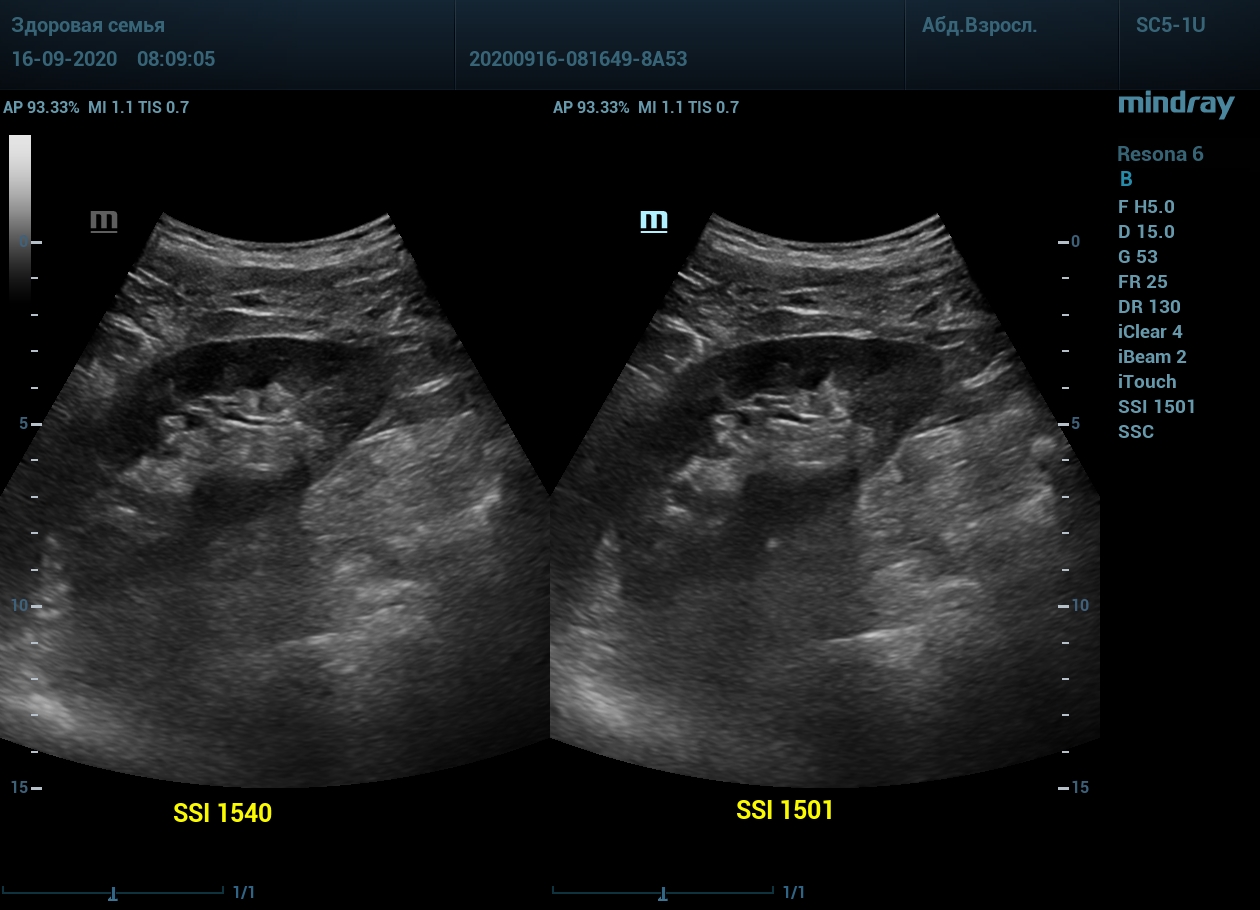

Примеры изображений:

2. Абдоминальный доступ левой почки. После калибровки скорости, дальний от датчика контур почки становится четким и контрастным.